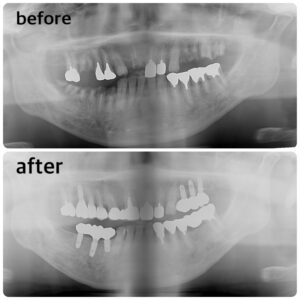

インプラント症例写真

先生が以前ご担当された患者様のインプラントの症例写真になります。

こちらの患者様は、下3本 上4本のインプラントをされました。

とてもきれいで自然な仕上がりになりました😌✨